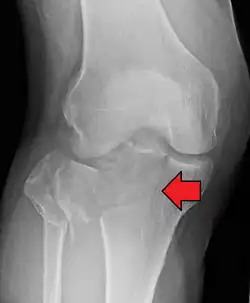

Lipohemarthrosis (presence of fat and blood from bone marrow in the joint space after an intraarticular fracture) seen on X-ray in a person with a subtle tibial plateau fracture -

Lipohemarthrosis due to a tibial plateau fracture -

A tibial plateau fracture seen on X-ray